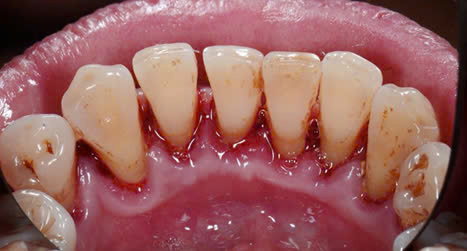

Một số hình ảnh trước và sau khi lấy cao răng:

Case 2: